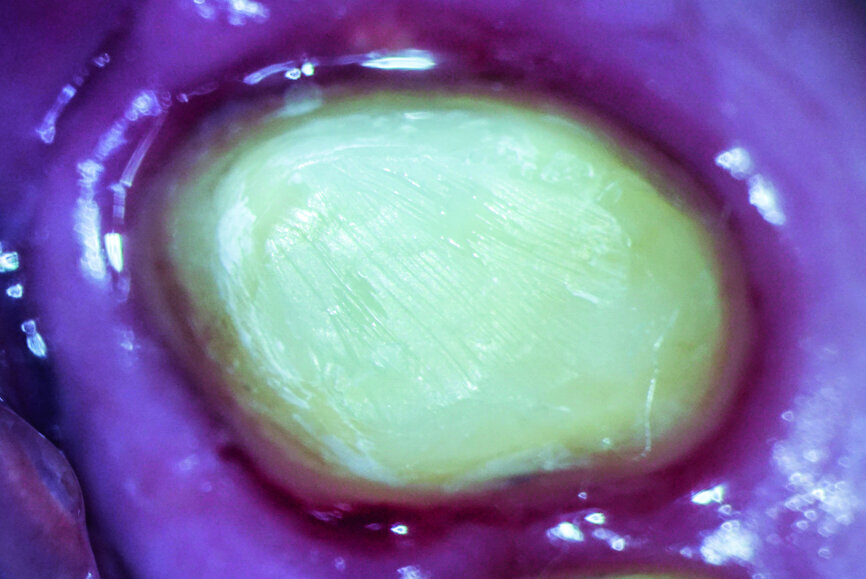

The patient who is the focus of our discussion came to our office reporting intense pain in response to hot and cold stimuli in the left maxilla (Fig. 1). He described the pain as being spontaneous at times and that in order for it to subside administration of anti-inflammatory medication was required. Upon examination, an accurate diagnosis was established of symptomatic irreversible pulpitis affecting tooth #27. The patient had had the tooth prepared for a crown sometime in the last 60 days (Fig. 2), but unfortunately the treatment was not completed for unknown reasons. Caries seemed to be absent; therefore, a minimally invasive approach was planned. Most likely, the pathology was caused by either trauma or an iatrogenic event.

After isolation of the tooth (Fig. 3), an access cavity was created using high-speed diamond burs and ultrasonic tips (Figs. 4–8). Pre-flaring in the coronal and middle thirds was done with the HyFlex EDM 25 instrument (at a torque of 4 Ncm and a speed of 500 rpm). It is a proven fact that pre-flaring allows an increase in the instrument size that binds in the root canal, irrespective of the discrepancy between the size of the file and anatomical diameter. [19–21] Afterwards, canal scouting was performed using an ISO size 10 stainless-steel K-file up to working length. Upon establishing the working length, with the help of an apex locator, the 10/05 EDM file (glide path file) was used up to working length (at a torque of 3 Ncm and a speed of 300 rpm). Subsequently before finishing the preparation with the 25 EDM file, the 20/05 EDM (preparation file) was used to full working length (at a torque of 3 Ncm and a speed of 400 rpm). At this point, the working length was confirmed again with an ISO size 20 NiTi K-file. Root canal shaping was completed with the 25 EDM file, which was inserted to full working length (at a torque of 3 Ncm and a speed of 400 rpm; Figs. 9–12).